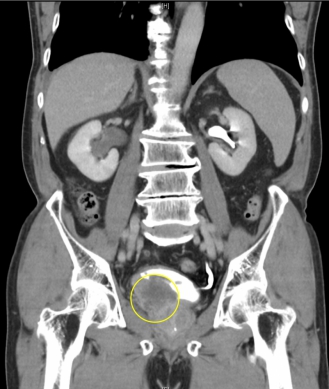

七旬男子至員基醫院求診而揪出膀胱癌(圓圈處)。(照片員基提供)

〔記者周為政、林碧珠員林報導〕七旬男子血尿至員基醫院求診,醫師揪出膀胱癌,即時開刀手術而確保健康。 員基醫院說,七十餘歲男子發現血尿,起初不以為意,認多喝水就會獲得改善,但症狀未見好轉,乃至員基...